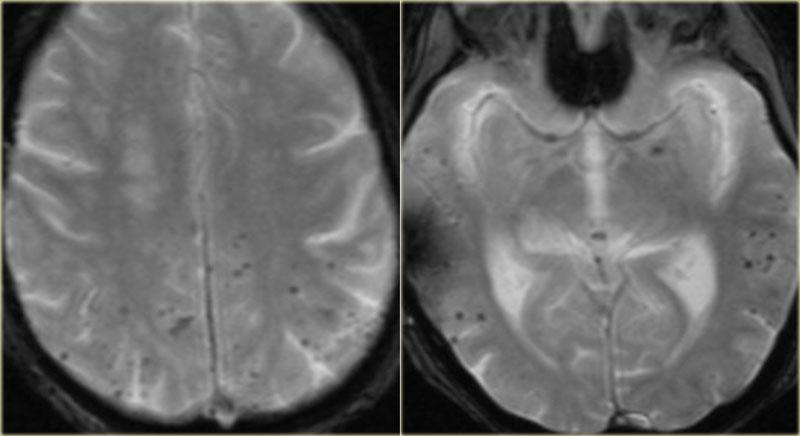

Chuỗi xung T2W và T2* gradient echo cho thấy nhiều cavernoma.

Lưu ý hình ảnh “bỏng ngô” với vành hemosiderin ngoại vi trên chuỗi xung T2W.

Các tổn thương gần như hoàn toàn màu đen trên chuỗi xung gradient echo do xảo ảnh blooming.

Chuỗi xung T2* và hình ảnh trọng số độ nhạy từ (SWI) làm tăng đáng kể độ nhạy của MRI trong việc phát hiện các cavernoma nhỏ.

Năm chấm đen ở bán cầu đại não trái trên chuỗi xung T2* cũng là cavernoma và không thể nhìn thấy trên chuỗi xung T2W.

Chẩn đoán phân biệt các vi xuất huyết

Ở bệnh nhân có nhiều chấm đen nhỏ, chẩn đoán phân biệt bao gồm:

- Cavernoma

- Bệnh mạch máu não dạng tinh bột (CAA)

Các vi xuất huyết không đối xứng ở vị trí ngoại vi, gặp ở người cao tuổi không tăng huyết áp có xuất huyết thùy não.

CAA thường gặp ở bệnh nhân sa sút trí tuệ. - Vi xuất huyết do tăng huyết áp

Các vi xuất huyết ở bệnh nhân tăng huyết áp, trẻ tuổi hơn so với bệnh nhân CAA - Tổn thương sợi trục lan tỏa (DAI)

Xuất huyết sau chấn thương ở thể chai, chất trắng dưới vỏ và thân não.

Tổn thương sợi trục lan tỏa (DAI)

Một người đi xe đạp 46 tuổi nhập viện với triệu chứng co giật sau khi bị xe ô tô đâm.

Hình ảnh CT chỉ cho thấy xuất huyết dưới nhện tối thiểu (mũi tên).

MRI được thực hiện vài tuần sau chấn thương do bệnh nhân có thay đổi nhân cách.

Chuỗi xung T2* cho thấy nhiều ổ lắng đọng hemosiderin tại vùng ranh giới giữa chất xám và chất trắng, phù hợp với tổn thương sợi trục lan tỏa (DAI).

Lưu ý vị trí của các vi xuất huyết này khác với các ổ xuất huyết CAA nằm ở ngoại vi.